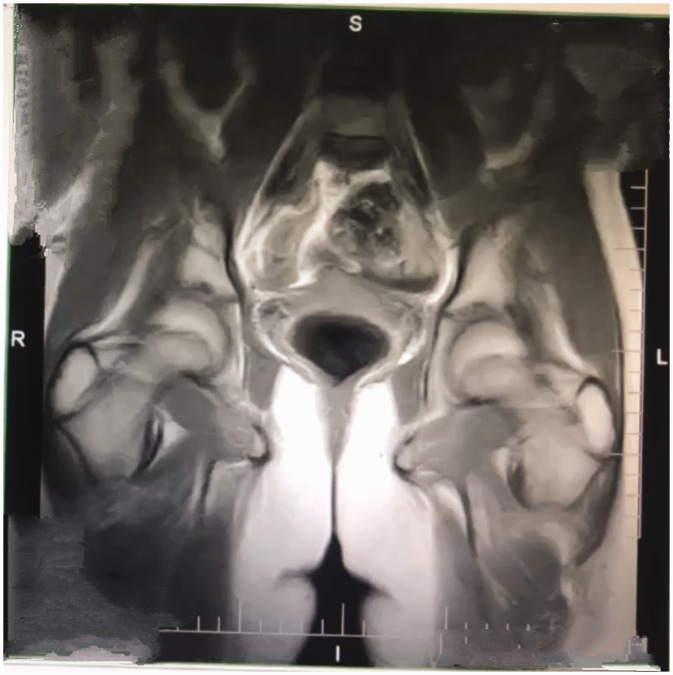

Swyer综合征是一种完全性腺发育不良的形式,是一种罕见的遗传病,其表型女性表现为46,xy核型。15岁女孩,第二性征发育不全,闭经。实验室检查显示促卵泡激素水平升高,雌二醇水平低,同时影像学检查发现子宫和性腺小。染色体分析证实为46,xy核型。患者接受激素替代治疗,青春期发育明显,8个月内达到Tanner期3。这个病例强调了早期识别,染色体分析和量身定制的管理在斯威耶综合征的重要性。基于激素治疗、生育咨询和心理支持的多学科方法对改善患者预后至关重要。作为叙利亚首例Swyer综合征病例报告,本研究强调需要提高对这种罕见疾病的临床认识,并扩大原发性闭经的鉴别诊断。

Swyer syndrome, a form of complete gonadal dysgenesis, is a rare genetic condition in which phenotypic females exhibit a 46,XY karyotype. A 15-year-old girl presented with underdeveloped secondary sexual characteristics and amenorrhea. Laboratory investigations revealed elevated follicle-stimulating hormone levels and low estradiol levels, while imaging identified a small uterus and gonads. Chromosomal analysis confirmed a 46,XY karyotype. The patient was treated with hormone replacement therapy, resulting in significant pubertal development, reaching Tanner stage 3 within 8 months. This case highlights the importance of early recognition, chromosomal analysis, and tailored management in Swyer syndrome. Multidisciplinary approaches based on hormonal therapy, fertility counseling, and psychological support are crucial to improving patient outcomes. As the first case report of Swyer syndrome in Syria, this study underscores the need for heightened clinical awareness of this rare condition and widens the differential diagnosis for primary amenorrhea.